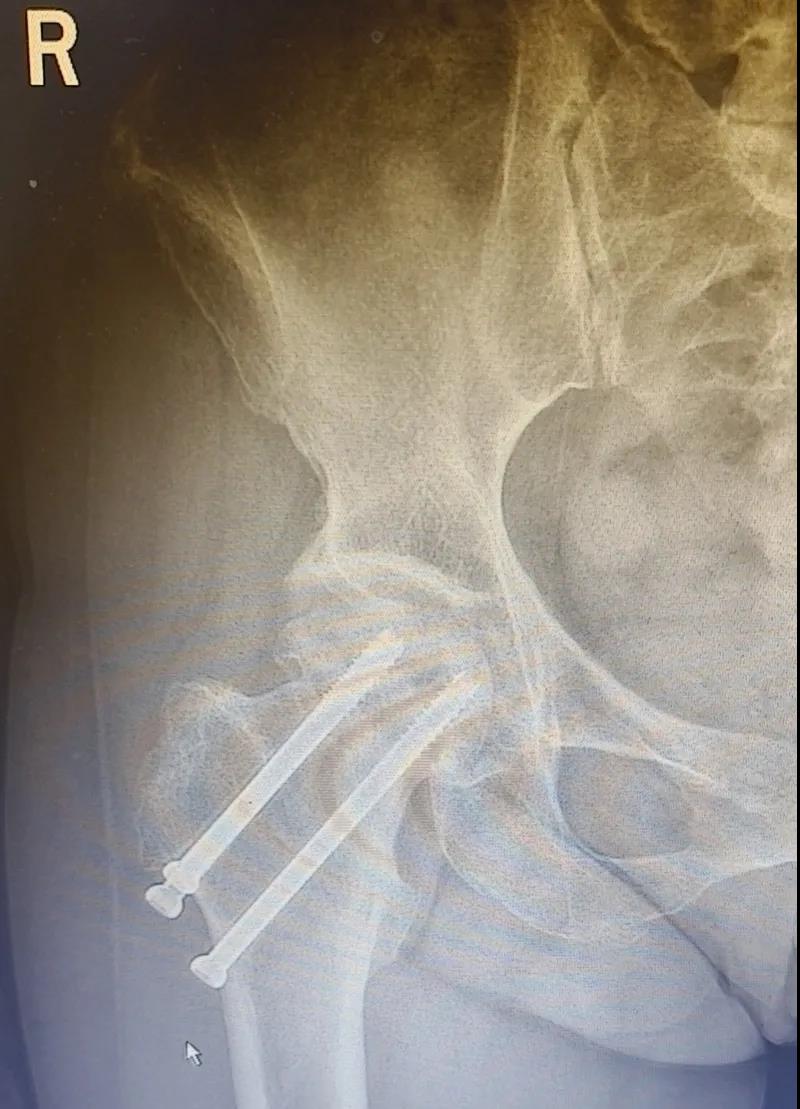

據李女士自述,自己于3年前因外傷致右股骨頸骨折,當時在其他醫(yī)院做了右股骨頸骨折閉合復位螺釘內固定術,一年后右髖出現疼痛并逐漸加重,且休息不能緩解,行走時就像有座山壓身上一樣。

結合病癥表現及影像顯示,李女士被診斷為“右股骨頸骨折術后股骨頭壞死”,需要盡快做手術。

(△術前影像,右股骨頸骨折內固定術后股骨頭壞死)